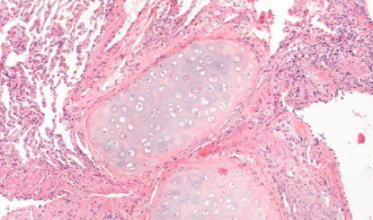

- Le Data Challenge DigiLUT : porté par l’Hôpital Foch, la compétition à été lancée en juin 2024 et avait pour objectif de développer un modèle d’apprentissage automatique capable de prédire la présence de signes de rejet chez un patient greffé pulmonaire. Les compétiteurs ont disposé d’une base de données anonymisées comprenant 2 500 lames d’anatomopathologie numérisées de biopsies pulmonaires de patients greffés. L’objectif final vise à automatiser l'identification des zones pathologiques dans les tissus pulmonaires, un élément clé pour améliorer la reproductibilité des diagnostics et ainsi mieux gérer la prise en charge des patients transplantés.

Après deux mois de compétition ayant rassemblé plus de 250 équipes à l’échelle internationale, plus de 1 200 modèles ont été développés et testés pour tenter de répondre à la problématique.

Un événement de remise des prix a eu lieu le 14 novembre 2024 à PariSanté Campus, le replay de l'événement est disponible ici.

Retrouvez les algorithmes lauréats du Data Challenge DigiLut publiés en open source ici.